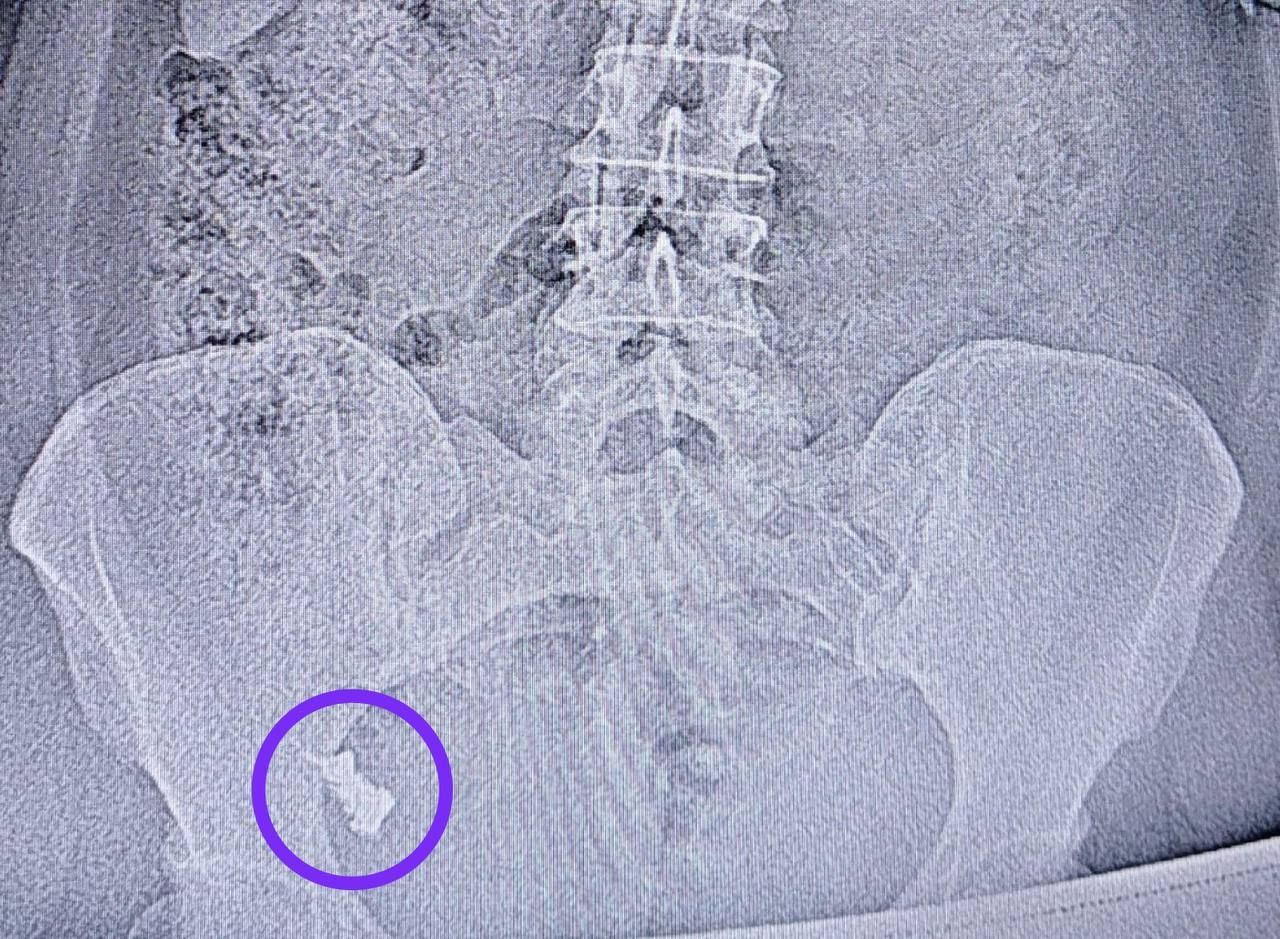

Эндоскописты Республиканской клинической больницы извлекли из кишечника 50-летней жительницы Казани случайно проглоченный ей зубной протез. Пациентка несколько раз отказывалась от ФГДС и госпитализации, полагая, что предмет выйдет естественным путем, рассказали в пресс-службе медучреждения.

Но через неделю инородный объект застрял в области перехода тонкой кишки в толстую, и пациентку госпитализировали. Ей провели колоноскопию под анестезией и удалили из ее организма протез.